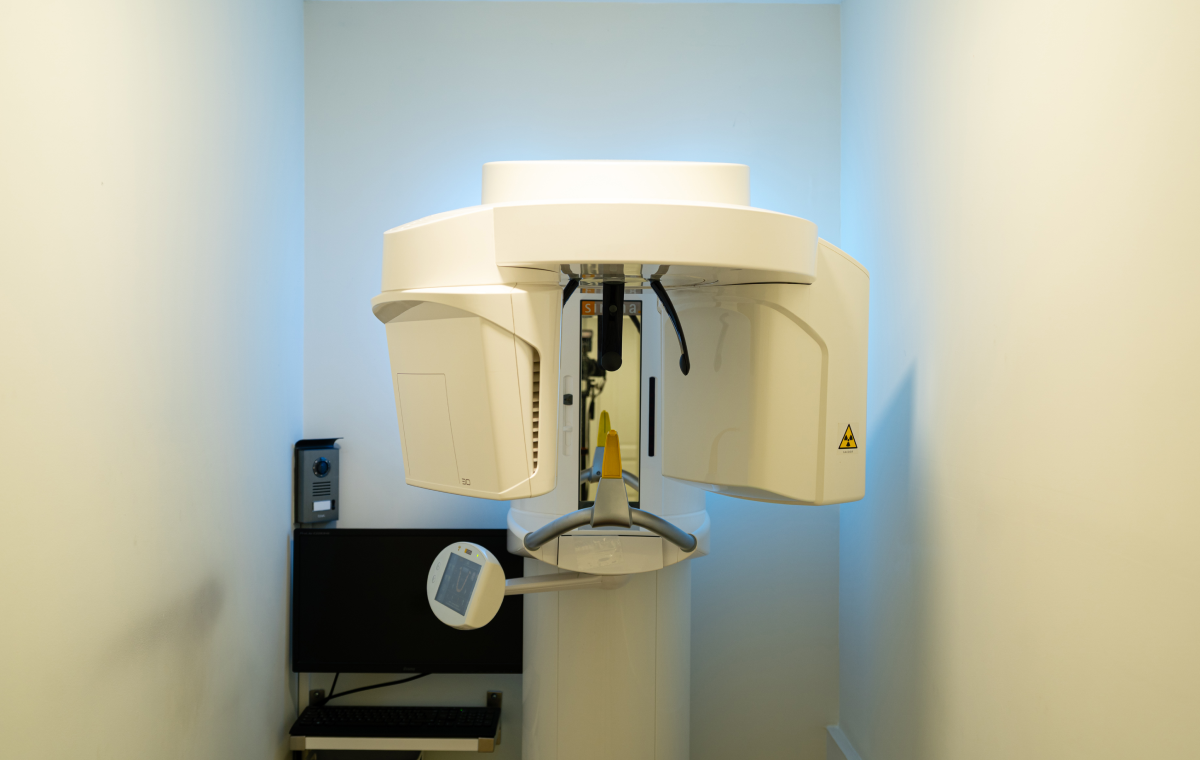

Radiographie pano 2D et 3D

La radio Panoramique est une technologie permettant l’exploration précise des structures osseuses et dentaires en trois dimensions. Une technologie essentielle dans l’élaboration d’un plan de traitement et pour le suivi de chaque patient.